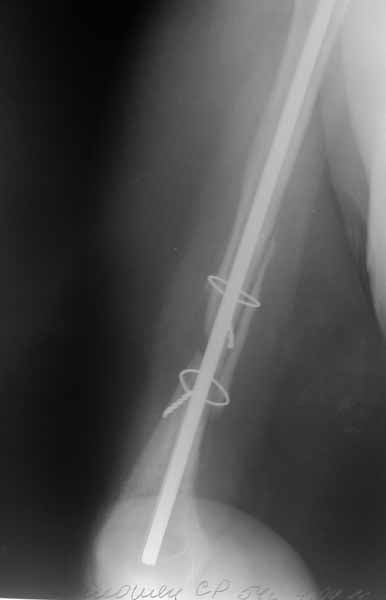

[Ortho] Застарелый вывих головки плечевой кости

Прошу прощения за отсутствие всех рентгенограмм.

Выбрасываю. По поводу гипсовой повязки: пациентка находилась в повязки типа Дезо. Плечо в приведении.